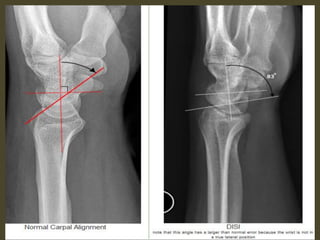

A simple approach is to consider the lunate

which is usually the easiest carpal bone to

visualize on a lateral wrist image. If the

lunate is abnormally tilted in a dorsal

direction on a standard lateral wrist image,

a DISI should be considered. If the lunate is

abnormally tilted in a volar direction a VISI

should be considered. DISI is due to

disruption of the scapho-lunate articulation.

VISI is secondary to disruption of the luno-

triquetral articulation.

DISI deformity.

DISI.